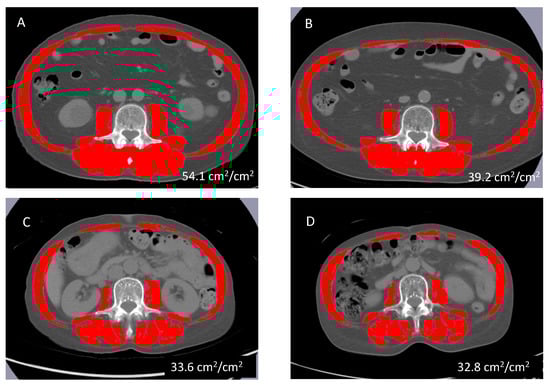

Pretreatment CT images were analyzed with SliceOMatic software (version 4.3; TomoVision, Montreal, QC, Canada) to calculate the skeletal muscle index (SMI; cm2/m2). The SMI was calculated by dividing the area of muscle mass at the third lumbar spine on the CT images by the square of the height (Figure 1). The cut-off values for SMD were set for each sex based on a previous report involving Japanese patients (male < 42 cm2/m2; female < 38 cm2/m2) [].

Figure 1.

Axial CT image of the third lumbar spine region with skeletal muscles highlighted in red. CT images of a 70-year-old man with non-SMD before (A) and after 25 cycles of AZA (B); CT images of a 68-year-old woman with SMD before (C) and after 11 cycles of AZA (D). Abbreviations: CT, computed tomography; SMD, skeletal muscle depletion; AZA, azacitidine.